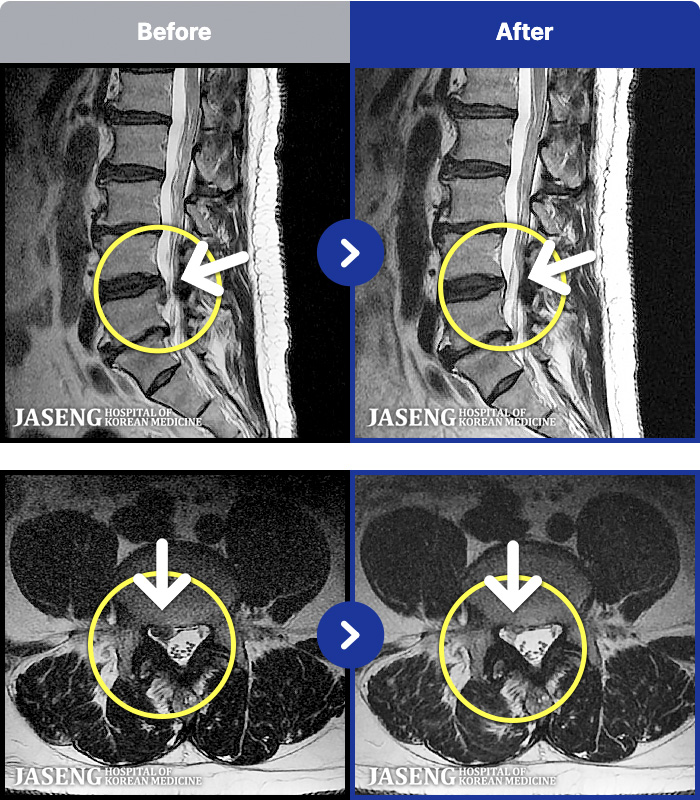

MRI ġ

54 MRI ũ ʸ Ȯϼ.

[_㸮ũ] 㸮